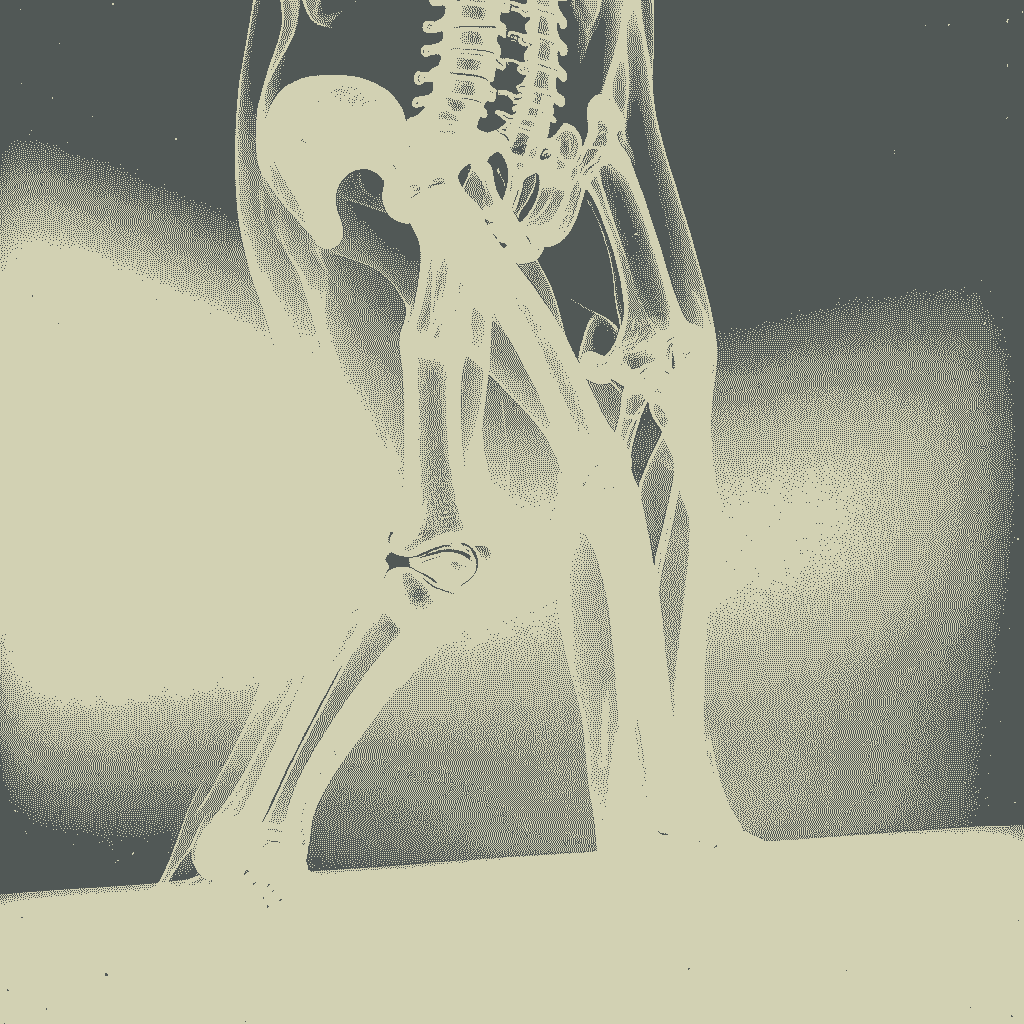

골반 및 척추, 사지 방사선 치료는 악성 종양 치료의 중요한 방법입니다. 골반 부위 치료는 종양의 위치와 진행 정도에 따라 계획이 달라지며, 주변 정상 조직 보호를 최우선으로 고려합니다. 척추와 사지 치료는 대부분 전이된 종양을 대상으로 통증 완화 및 증상 경감을 목표로 합니다. 두 부위 모두 환자 상태에 맞춘 개별적인 치료 계획이 중요하며, 모의 치료 과정을 통해 최적의 조사 방법과 선량을 결정합니다. 본문에서는 부위별 치료 방법과 모의 치료 과정에 대해 자세히 설명하고자 합니다.

척추 및 사지 방사선 치료

척추 및 사지 방사선 치료는 대부분 전이된 종양을 대상으로 시행됩니다. 따라서 완치보다는 통증 경감이나 증상 완화 목적의 대증적 치료가 주를 이루며, 정해진 치료 방법보다는 환자 상태에 따라 치료 계획을 세우게 됩니다. 특히 대증적 치료 시에는 방사선 치료로 인한 부작용이 발생하지 않도록 선량 및 치료 계획을 신중하게 수립해야 합니다.